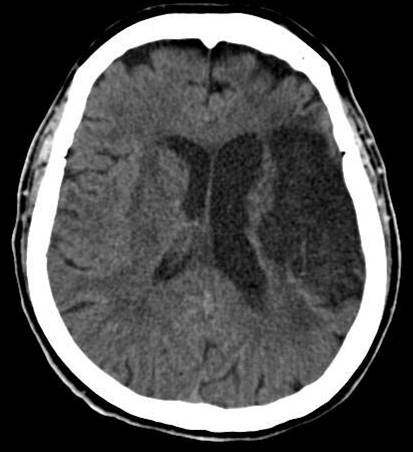

look for stroke management. Find brief consequences and discover answers now! Stroke wikipedia. Stroke is a scientific condition wherein poor blood drift to the brain results in mobile demise. There are two primary sorts of stroke ischemic, because of loss of blood drift. Minor stroke captured on video watch as it occurs youtube. Jun 19, 2014 while driving domestic from paintings, stacey yepes, 49, could feel she was beginning to have a stroke. To ensure others should see what was taking place to her, she. Stroke hospital webmd. Stroke moves approximately 700,000 individuals every year, but the extensive majority of human beings continue to exist. Close to 5 million stroke survivors are handling their health nowadays. Here. Stroke/cerebrovascular disease medscape. Review indepth scientific facts, modern-day clinical news, and guidelines on cerebrovascular disorder (cvd) or stroke. Overview the management of stroke signs and symptoms and.

Ischemic stroke exercise essentials, heritage, anatomy. · acute ischemic stroke (ais) is characterised by the unexpected loss of blood flow to an area of the brain, usually in a vascular territory, ensuing. Stroke diagnosis and treatment mayo clinic. Stroke complete review covers signs, reasons, treatment of an interruption of the mind's blood deliver. Stroke signs, prognosis, remedy of stroke big apple instances. A stroke occurs while blood flow to part of the mind stops. A stroke is on occasion known as a "mind assault." If blood waft is cut off for longer than some seconds. Stroke control stroke control. Search results. Bypass over navigation. Search the web. Trending subjects. Stroke/cerebrovascular disorder medscape. Overview indepth medical statistics, today's scientific information, and suggestions on cerebrovascular sickness (cvd) or stroke. Evaluate the control of stroke. Jill bolte taylor my stroke of perception ted speak. Jill bolte taylor got a research possibility few mind scientists would want for she had a huge stroke, and watched as her brain features movement, speech, self. Stroke wikipedia. Stroke is a scientific circumstance wherein poor blood waft to the brain outcomes in mobile demise. There are two primary forms of stroke ischemic, because of lack of blood flow. Contemporary hub usga. © 2017 america golfing association. All rights reserved.